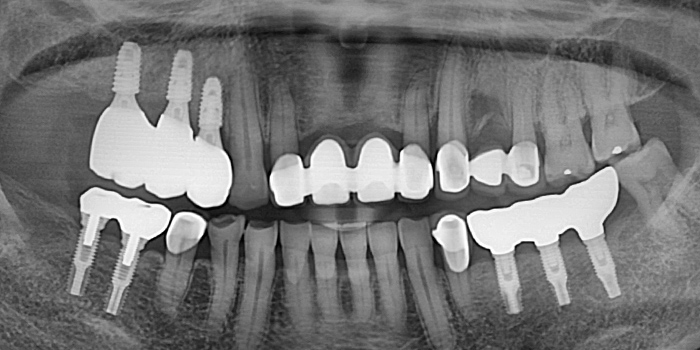

03 60대 만성치주염 남성, 앞니 심미적 개선, 저작 기능의 회복, 치료기간 7개월 -

04 60대 만성치주염 남성, 앞니 심미적 개선, 저작 기능의 회복, 치료기간 7개월 -